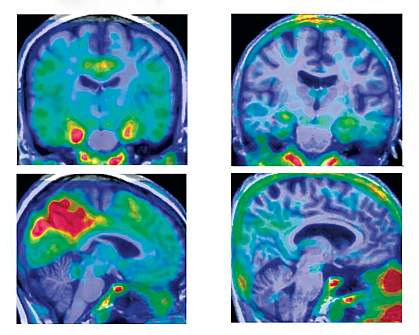

The researchers conducted brain imaging on two of the participants. The scans revealed less buildup of tau protein tangles and preserved metabolic activity in brain regions associated with AD. Tau tangles are thought to contribute to the death of brain cells in AD. However, intriguingly, as seen in the first woman studied, the brains had high levels of amyloid-β plaque, another hallmark of AD.